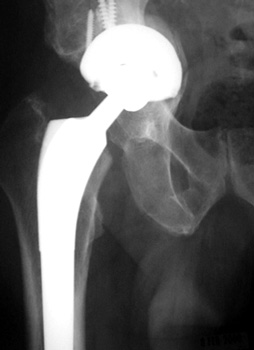

SUBSIDENCE - loose femoral prosthesis with interface widening,

osteolysis Gruen zone 6, cement fracture left femoral component

and osteolysis, with femoral component in valgus.